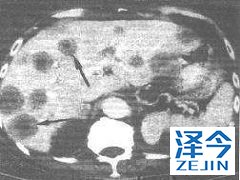

他的肿瘤测序证明了MET基因的突变。病例2在诊断时有乳头状肾癌,脑转移。在脑肿瘤放射后,给予血管内皮生长因子受体酪氨酸激酶抑制剂3年。除了大脑外,所有部位都控制着这种疾病;几个新的脑转移瘤需要新的放射治疗方法。这种疾病最终在所有转移部位进展,包括他的大脑,并且他有几种神经系统症状。给予卡博替尼并迅速诱导临床改善;进一步的计算机断层扫描和脑磁共振成像显示显着的肿瘤消退。在肿瘤分析中未观察到MET基因突变或扩增。